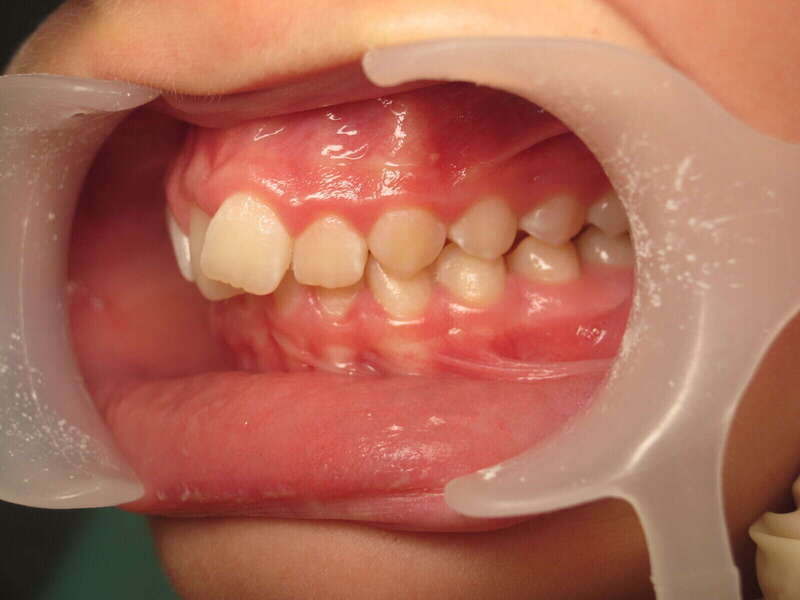

Cas n°1 traité par aligneurs (interception) - enfant

Ce cas d’interception chez un enfant de 8 ans démontre l'efficacité des aligneurs pour corriger des troubles fonctionnels précoces. Le diagnostic présentait des inversions d'articulé provoquant une déviation de la mandibule vers la gauche et un décalage des milieux.

Grâce à une coopération exemplaire et un traitement totalement indolore, l'expansion de l'arcade a permis de recentrer la mâchoire. Cette intervention a littéralement remis la croissance sur les rails, neutralisant le risque d'asymétrie faciale squelettique.